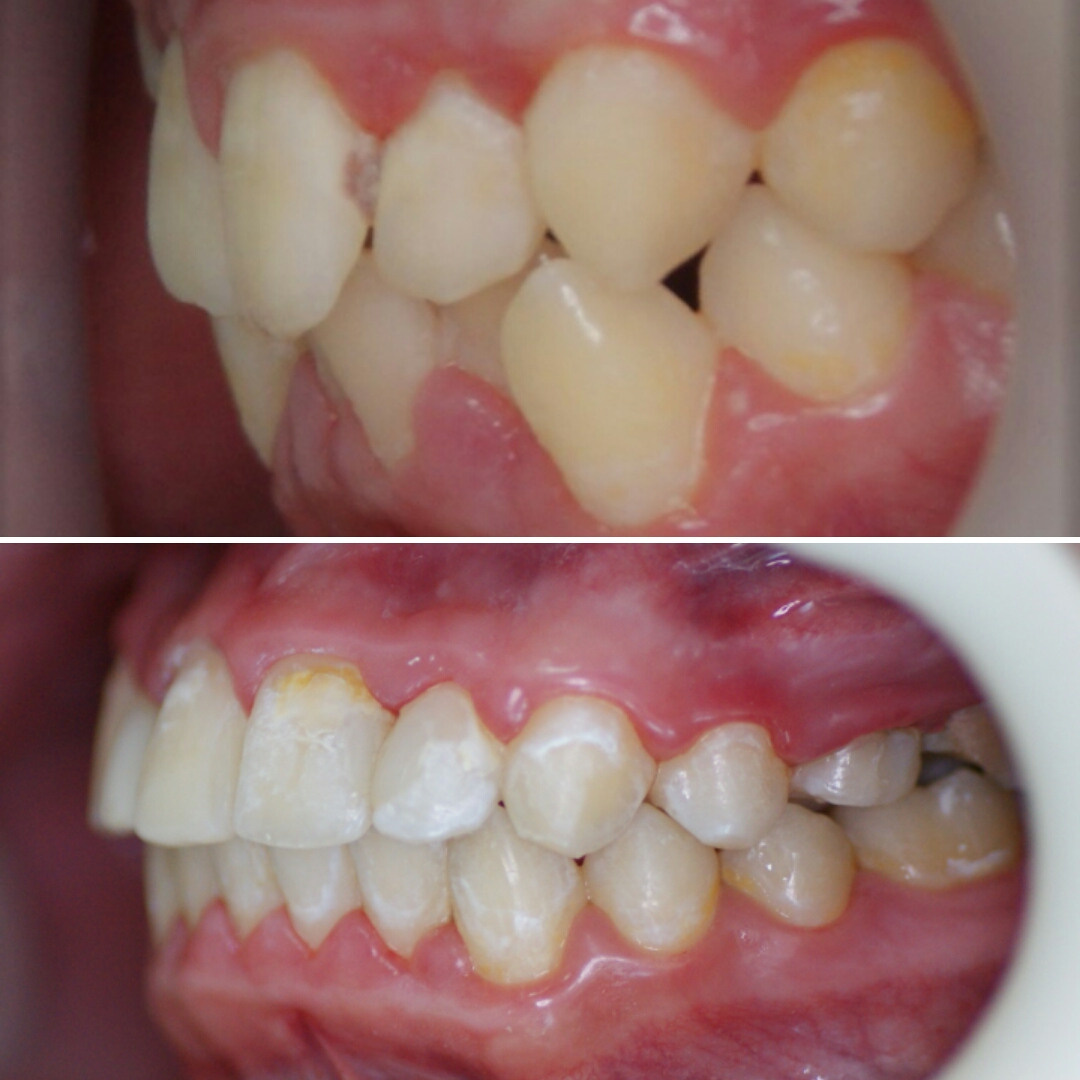

Эта фраза знакома многим ответственным родителям, которые привели на приём к ОРТОДОНТУ своего ребёнка в 5-10 лет, заподозрив проблему или понимая, что места постоянным зубам откровенно не хватает! Горькая правда в том, что брекеты - не волшебное средство от всех проблем, они "расставляют" зубы внутри сформированого объёма челюсти, но никак не влияют на её рост. Родители ждут, а тем временем драгоценное время, когда ребёнок растёт, уходит... Во взрослом возрасте приходится удалять здоровые зубы или прибегать к ортогнатической хирургической операции. 📸 На фото узкая нижняя челюсть, места постоянным зубам нет, боковые резцы прорезываются "вторым рядом".

🔷️ Промежуточный результат лечения на аппарате Марко Роса (6 месяцев). Пациенту 7 лет. Самое удивительное - как "отвечает" на лечение нижняя челюсть: расширяется, меняется её положение и корректируется дистальный прикус, выравниваются нижние зубы, хотя никаких аппаратов на нижней челюсти не было!

P.S. Каждый случай уникальный, чаще нижнюю челюсть мы всё таки расширяем тоже.